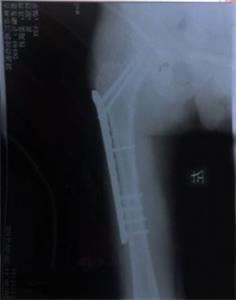

一直由姜跃军赡养的岳母患有肝病,因担心女婿而吐血病危住院。姜恳请“610”人员让他回家探望岳母,可他们完全不计人伦,不顾亲情与孝道地说:死了也不准!别说是岳母呀,就是亲妈死了也许能有一点点可能!万般无奈之下,姜跃军于9月20日从洗脑班二楼跳下,导致大腿骨粉碎性骨折。妻子得知消息去医院护理丈夫,结果遭国保大队张学涛、南城派出所曹凤坤、夏春林等大量警察绑架并拘留(拘留结束后又直接转到吉林市与舒兰市两处洗脑班继续迫害)。

'姜跃军腿部术后照片'

姜跃军腿部术后照片